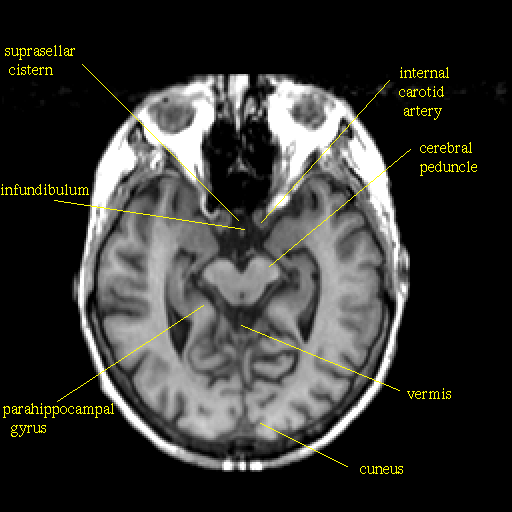

T1-weighted structural MR: Slice 22

Slice 22